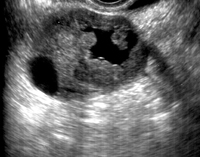

Cáncer de ovario (resonancia magnética nuclear)The incidence of uterine neck cancer remains constant at all ages in women, whereas ovarian cancer and endometrial cancer increase considerably during the perimenopausal years, and are by far the most frequent after the age of 50.

At present, mortality rates due to ovarian cancer clearly exceed combined mortality due to cancer of the uterine neck and endometrial cancer.